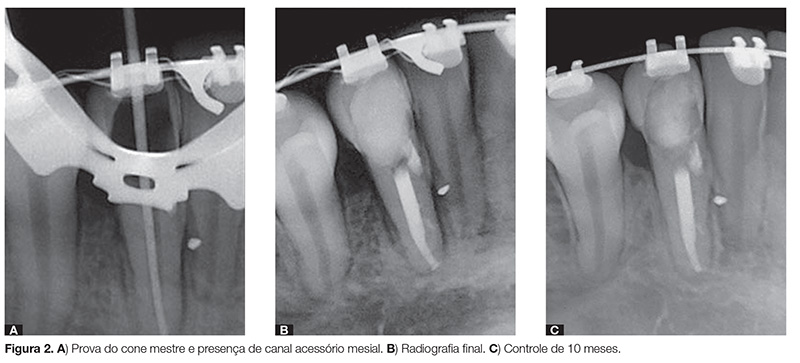

A medicação intracanal à base de pasta de hidróxido de cálcio foi aplicada por um período de 3 meses, sendo substituída a cada 45 dias. Após um período de 4 meses (outubro de 2010), realizou-se a obturação definitiva do canal radicular por meio da prova do cone de guta-percha (Fig. 2A), dando continuidade à obturação com cimento à base de hidróxido de cálcio e cones de guta-percha secundários por meio da técnica de condensação lateral seguida de condensação vertical (Fig. 2B). A câmara pulpar foi limpa e selada provisoriamente com bolinha de algodão estéril e Coltosol, se solicitando à paciente que procurasse seu dentista para realizar procedimentos restauradores definitivos pós-tratamento endodôntico.

Na Figura 2B é possível observar a obturação do canal radicular, o fechamento da perfuração com MTA e, na porção apical por mesial, a obturação de um canal secundário, que já era possível ser visualizado na Figura 2A.

Após 10 meses de conclusão do tratamento endodôntico, a paciente foi chamada para realizar a primeira proservação radiográfica. Na radiografia periapical intrabucal foi possível observar a integridade da região periapical com continuidade da lâmina dura, indicando clinicamente o reparo periapical (Fig. 2C).